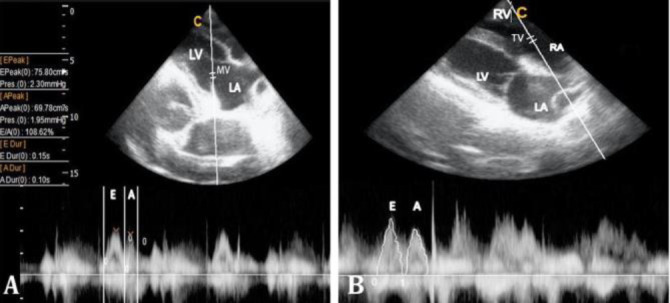

Echocardiography is a noninvasive, highly sensitive method for evaluating heart disease in veterinary medicine, crucial for measuring cardiac structures and functions. Despite its importance, limited data exist on sheep, particularly the Ghezel breed, a significant breed in Iran. This study aimed to establish normal echocardiographic values for Ghezel sheep, providing reference data for both clinical and research applications. We evaluated 15 healthy Ghezel sheep with a mean age of 16.50 ± 1.80 months and a mean weight of 42.69 ± 4.73 kg. Comprehensive clinical exams, biochemical and hematological tests and color Doppler echocardiography were performed. Descriptive results from standard right and left parasternal views in both longitudinal and transverse planes were obtained and compared to existing studies. The study successfully established pulse wave Doppler reference values for the Ghezel breed. These findings could be used in diagnosing heart disease in Ghezel sheep and would be beneficial in future research particularly in sheep used as an animal model for translation in human cardiac studies.